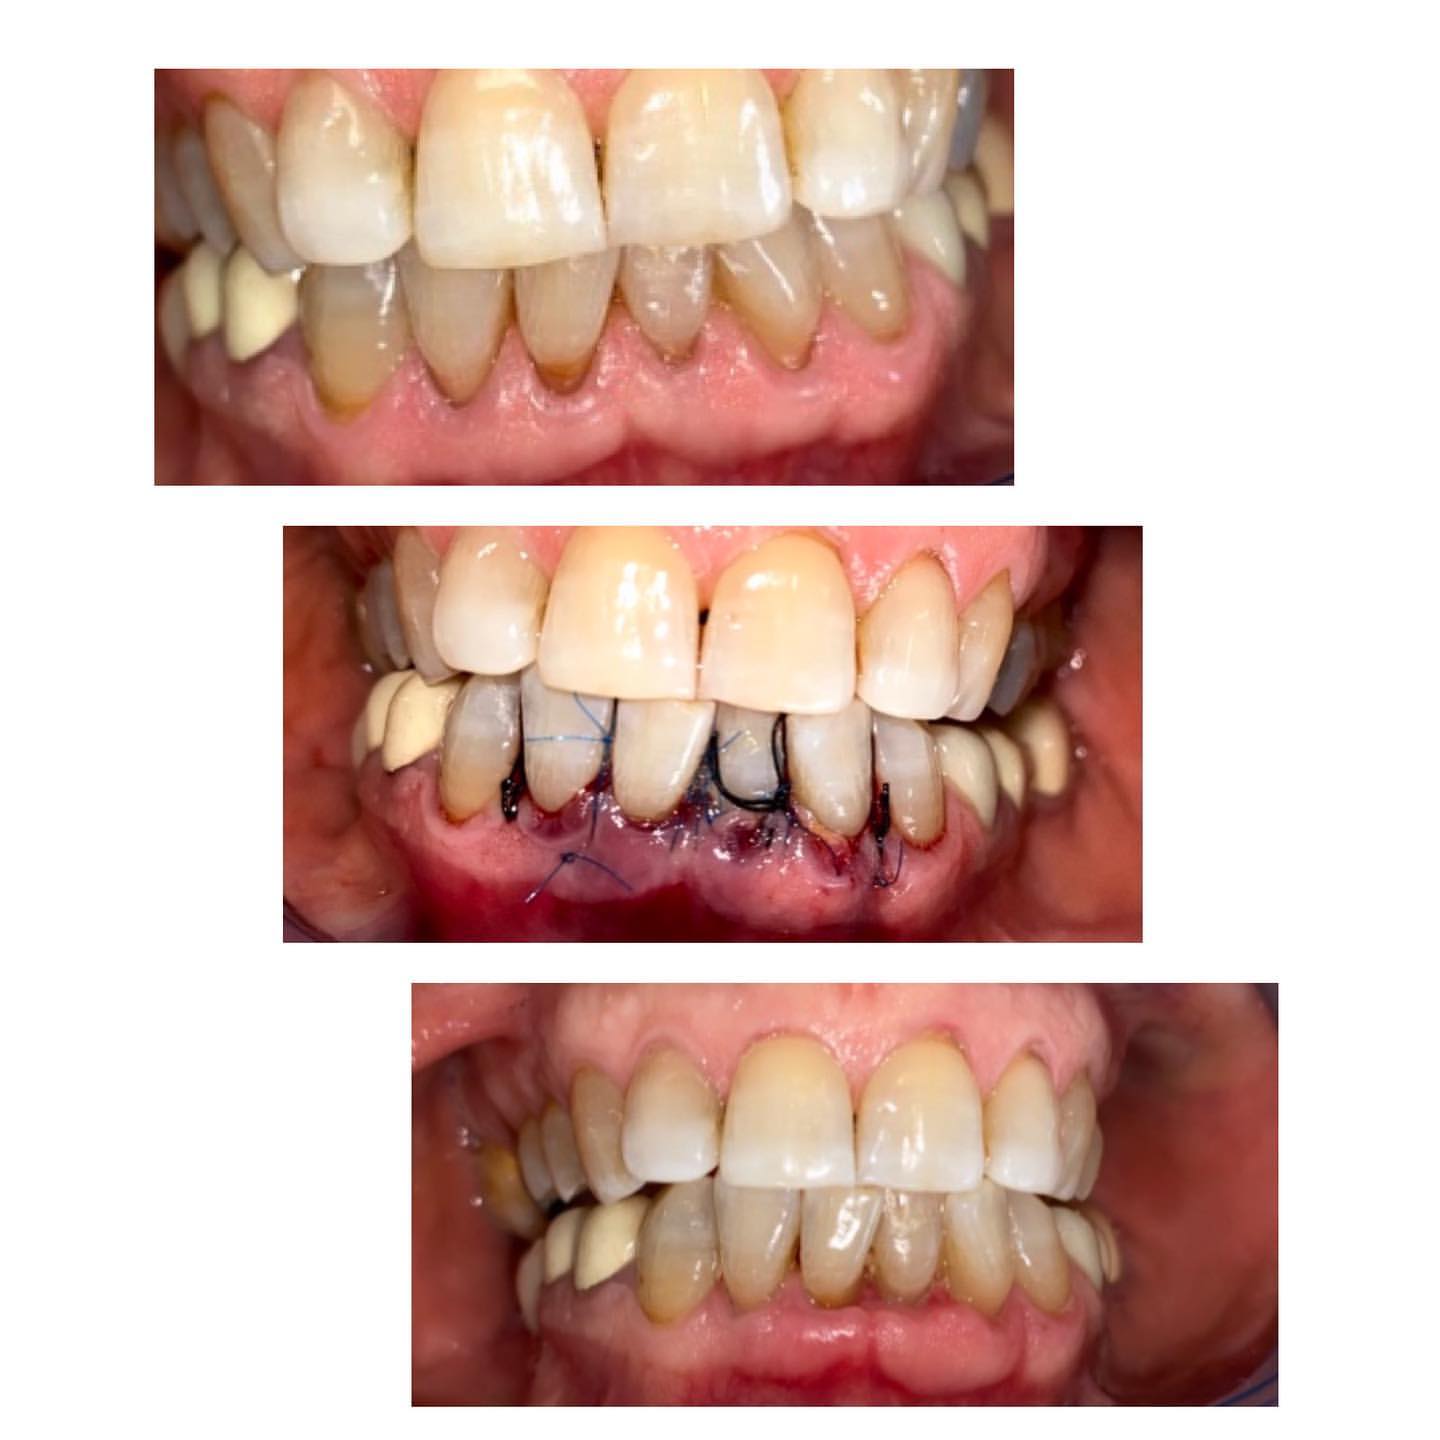

Diş əti çəkilməsi olan xəstənin tunel əməliyyatı ilə çəkilmənin qapadılması